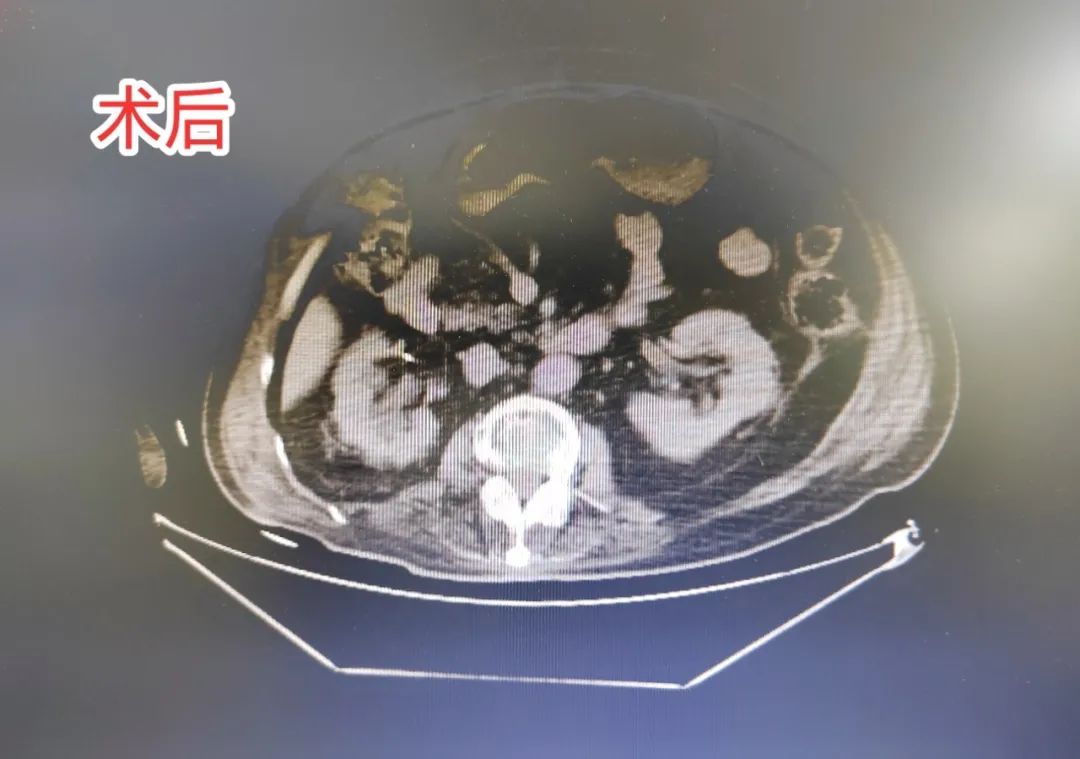

据家属反馈,许先生在疼痛剧烈时彻夜难眠,长期病痛折磨使其情绪高度焦虑。追溯病史,患者 30 余年前患上强直性脊柱炎,病程迁延下,双下肢关节僵硬挛缩,被迫长期卧床,腹部因缺乏运动及胃肠功能减弱明显膨隆,外观如充气「气球」。由于自主排尿功能丧失,长期依赖导尿管维持泌尿功能。经进一步泌尿系统超声、CT 造影等精密检查,确诊其右肾、膀胱存在多发性结石,同时尿道亦有结石嵌顿。

陈川聪主任及林寅生副主任带领泌尿一科团队进行充分讨论,全面评估患者情况后,制定了「右侧经皮肾镜碎石取石术 + 膀胱穿刺造瘘术 + 经膀胱造瘘膀胱结石钬激光碎石取石术」的手术方案。考虑到患者体位问题,术中采用仰卧位和左侧卧位交替进行取石。手术过程顺利,成功将最大约 2.0 cm×2.0 cm 的结石击碎取出,术中出血少,无结石残留,并顺利放置双 J 管和肾造瘘管。

术后,因强直性脊柱炎导致双下肢僵硬无法下床活动,需重点预防血栓形成。在泌尿一科全体医护人员的精心护理下,患者拔除尿管后,膀胱造瘘管引流通畅,恢复情况良好。目前,患者已经康复出院了。